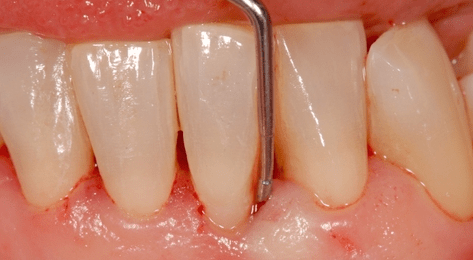

Nach Anästhesie des zu operierenden Bereichs wird eine intrasulkuläre Inzision mit mikrochirurgischen Skalpellklingen entlang der bukkalen Seite sowohl am betroffenen Zahn als auch an den jeweiligen benachbarten Zähnen durchgeführt. Die sulkuläre Inzision verläuft von der mesialen bis zur distalen Kantenlinie der Zähne. Im interproximalen Bereich des zu behandelnden Defekts wird die Papille entsprechend der modifizierten Papillenerhaltungstechnik auf der bukkalen Seite durchtrennt. Die bukkale Position der Papilleninzision wird so weit wie möglich unterhalb des Kontaktpunktes platziert.

Diese Inzision wird mit der intrasulkulären Inzision verbunden. Eine C-förmige vertikale Entlastungsinzision wird von der Kantenlinie des distalen Nachbarzahn bis in die Alveolarmukosa geführt. Darauffolgend wird ein Mukoperiostlappen auf der bukkalen Seite bis über die mukogingivale Grenzlinie gehoben. Auf der lingualen Seite wird vom beteiligten Zahn ausgehend eine intrasulkuläre Inzision durchgeführt und ebenfalls ein Mukoperiostlappen gehoben. Anschließend an die Präparation des externen Lappens wird ein interner gestielter Lappen gehoben, um einen schichtweisen Wundverschluss zu ermöglichen.

Von der Basis des präparierten externen Lappens wird eine interne horizontale Inzision vorgenommen. Zwei interne vertikale Inzisionen von der Lappenbasis aus in koronaler Richtung begrenzen die Breite des Lappens. Durch scharfe Präparation wird ein interner Spaltlappen präpariert. Man erhält einen bis zur mukogingivalen Grenzlinie partiellen inneren Lappen, der noch am koronalen Anteil des äußeren Lappens gestielt bleibt. Daraufhin wird Granulationsgewebe aus dem Defekt entfernt und die Wurzeloberfläche mit Hand- bzw. Ultraschallinstrumenten gereinigt.